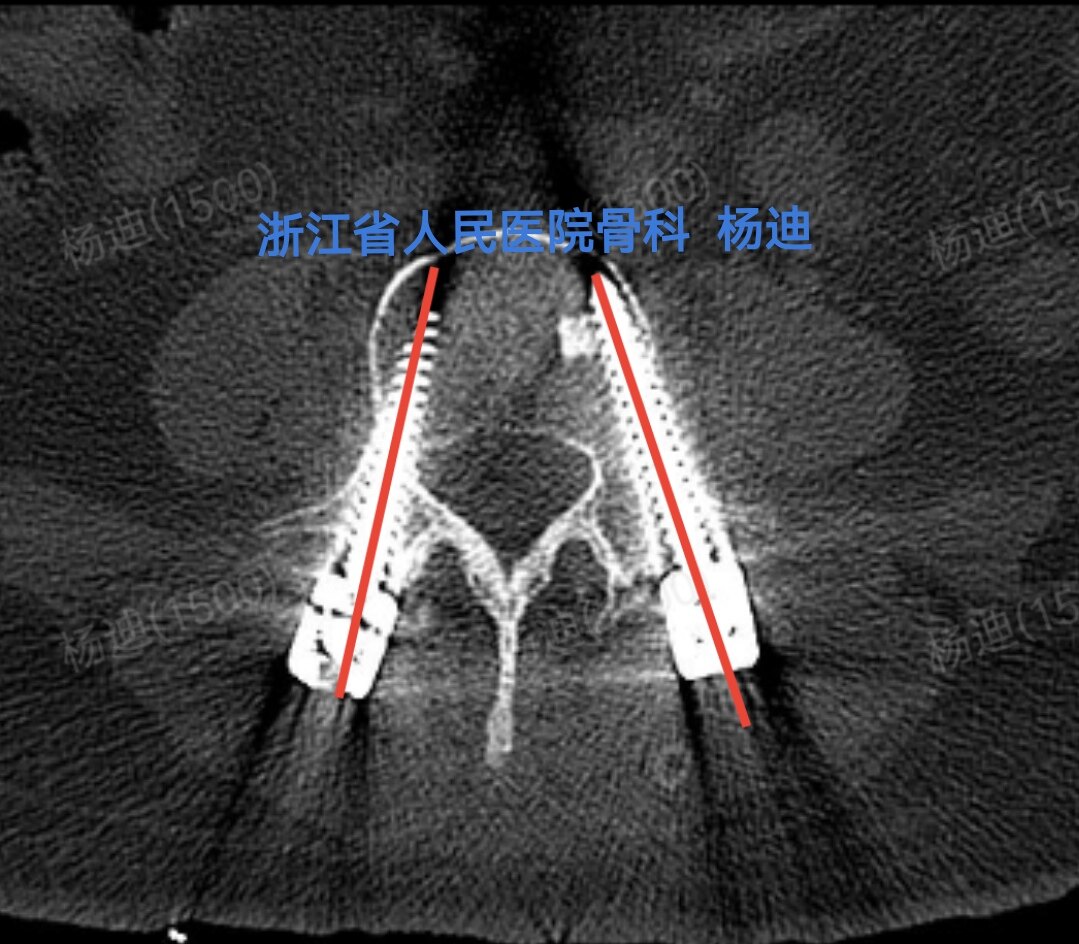

图为术后腰椎CT横断面,提示腰4椎体双侧螺钉位置及长度满意(红色直线)。

图为术后腰椎CT横断面,提示腰5椎体双侧螺钉位置及长度满意(红色直线)。